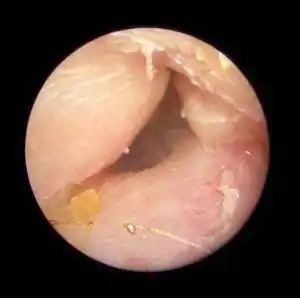

| Exostoses in the ear canal, as seen through otoscopy | |

Irritation from cold wind and water exposure causes the bone surrounding the ear canal to develop lumps of new bony growth which constrict the ear canal. Where the ear canal is actually blocked by this condition, water and wax can become trapped and give rise to infection. The condition is so named due to its prevalence among cold water surfers. Warm water surfers are also at risk for exostosis due to the evaporative cooling caused by wind and the presence of water in the ear canal.

Surfer's ear is the common name for an exostosis or abnormal bone growth within the ear canal. Surfer's ear is not the same as swimmer's ear, although infection can result as a side effect.